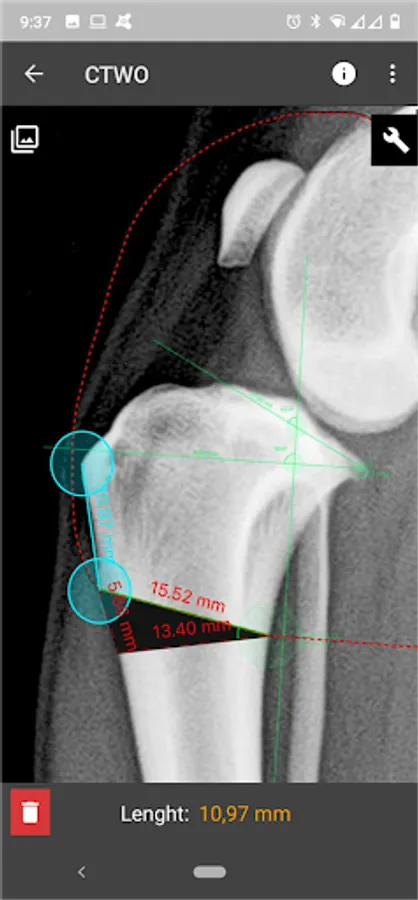

This is a useful tool for traumatology and orthopaedic surgical planning veterinary, including advanced techniques for treat canine anterior cruciate ligament (ACL) injuries (TPLO and CTWO).

3. Tools:

a) Linear Measure.

b) Radial measure/Circle draw.

c) Angle measure/Triangle draw.

e) Wedge cut, CTWO and angular osteotomies.